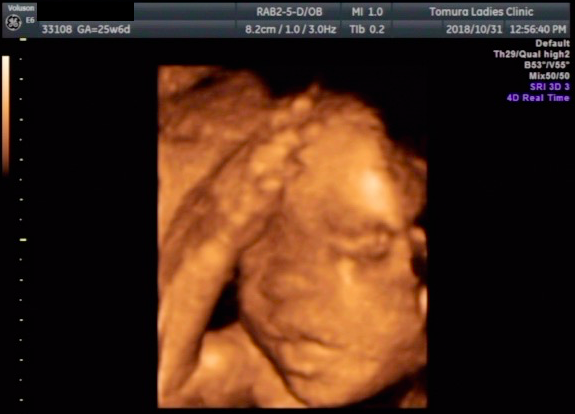

25週0日(25w0d・女の子)|こがも3 さん(27歳)

エコー写真撮影時のエピソード:

初めてちゃんと顔が見えたエコー写真なので、とても思い入れがあります。「鼻はママ似?パパ似かな?」と主人と話したこともいい思い出です。もちろん胎動があったので実感はしていましたが、顔が見えた事でより一層「この子が今お腹にいるんだ」と強く実感した事を覚えています。